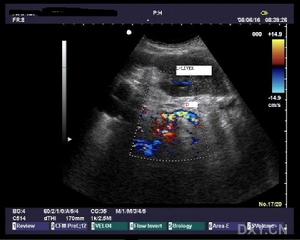

Bk8q7.jpg

(300 × 240像素,文件大小:12 KB,MIME类型:

胆总管结石